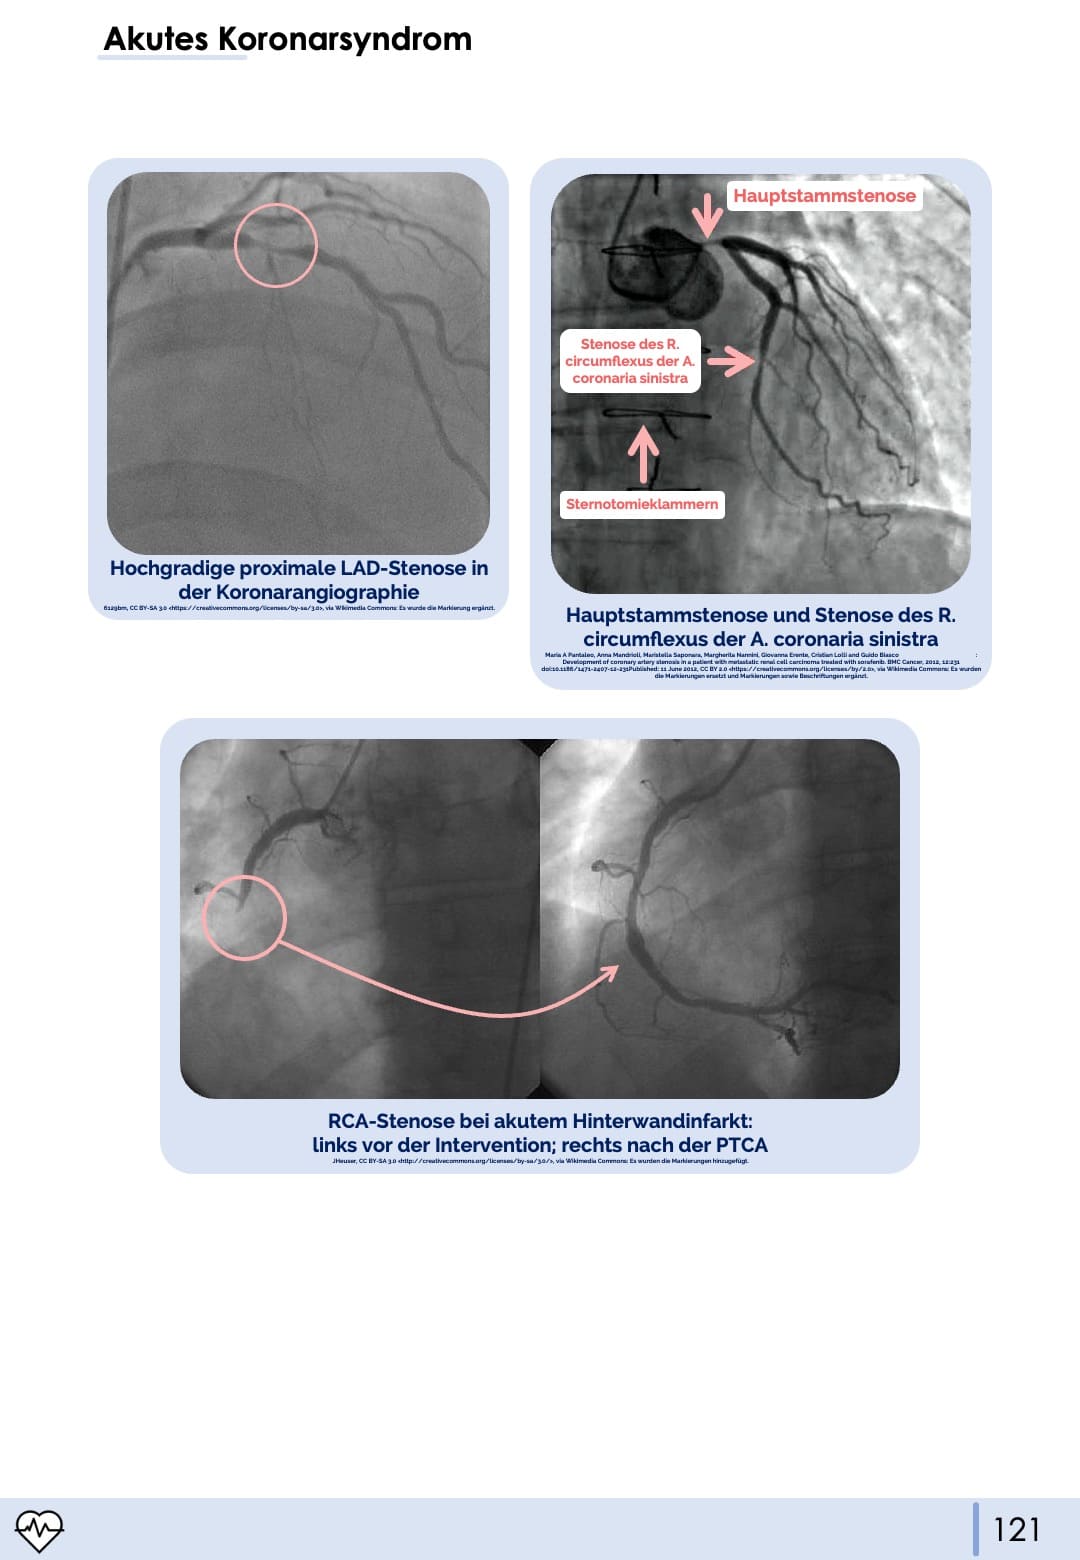

Akutes Koronarsyndrom

Akuter Myokardinfarkt